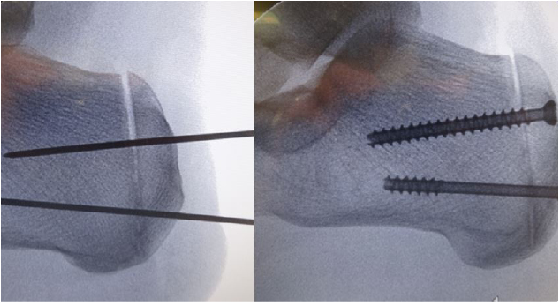

Preoperative templates are useful in determining the size of wedge resection with the Keck and Kelly dorsally-based wedge resection. The posterior cut should have a dorsal exit point just anterior to the Achilles tendon. The inferior apex of the wedge is posterior to the weightbearing area of the plantar calcaneal tuberosity. The anterior cut should be vertical on the lateral weightbearing image. A 7 to 9 mm wedge is generally needed to gain adequate correction depending on the individual anatomy of the calcaneus. One would place a linear incision on the lateral heel directly over the osteotomy site and intraoperative fluoroscopy-guided incision planning is useful in this regard. The surgeon can make a full thickness incision down to bone as the sural nerve and peroneal tendons are well anterior with this approach. Perform blunt dissection superiorly near the Achilles tendon and free the periosteum from the lateral and dorsal aspects of the calcaneus. This enables the surgeon to gain only enough exposure for the planned osteotomy.

One can employ intraoperative fluoroscopy to confirm that osteotomy exit points match the template. The surgeon can use an osteotomy guide over guide pins to facilitate cuts that are parallel from medial to lateral yet converge at the desired location at the plantar cortex. One would leave the plantar cortex intact for the final greenstick fracture. The strong plantar soft tissues act as a plantar hinge and prevent proximal migration of the posterior fragment in the sagittal plane. Dorsiflexing the foot manually allows the intact Achilles to compress the osteotomy. We used two cannulated cancellous screws to fixate the osteotomy.

Surgeons can achieve fixation with cannulated cancellous screws buried deep to the Achilles or external placement of Steinmann pins. Advantages of pin fixation include a less invasive approach near the Achilles tendon insertion and no residual hardware after removal at six weeks. Advantages of screw fixation include permanent fixation, compression of the osteotomy and no external protrusion of fixation.